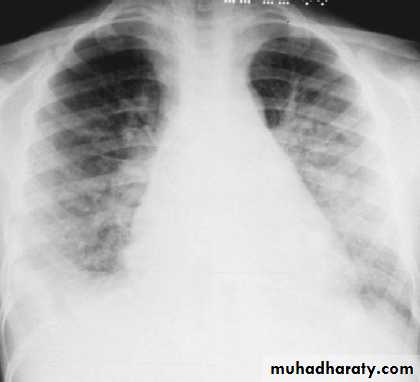

CXR is indicated in those with signs of heart failure or respiratory distress.

CXR of a patient with poststreptococcal glomerulonephritis showing pulmonary edema